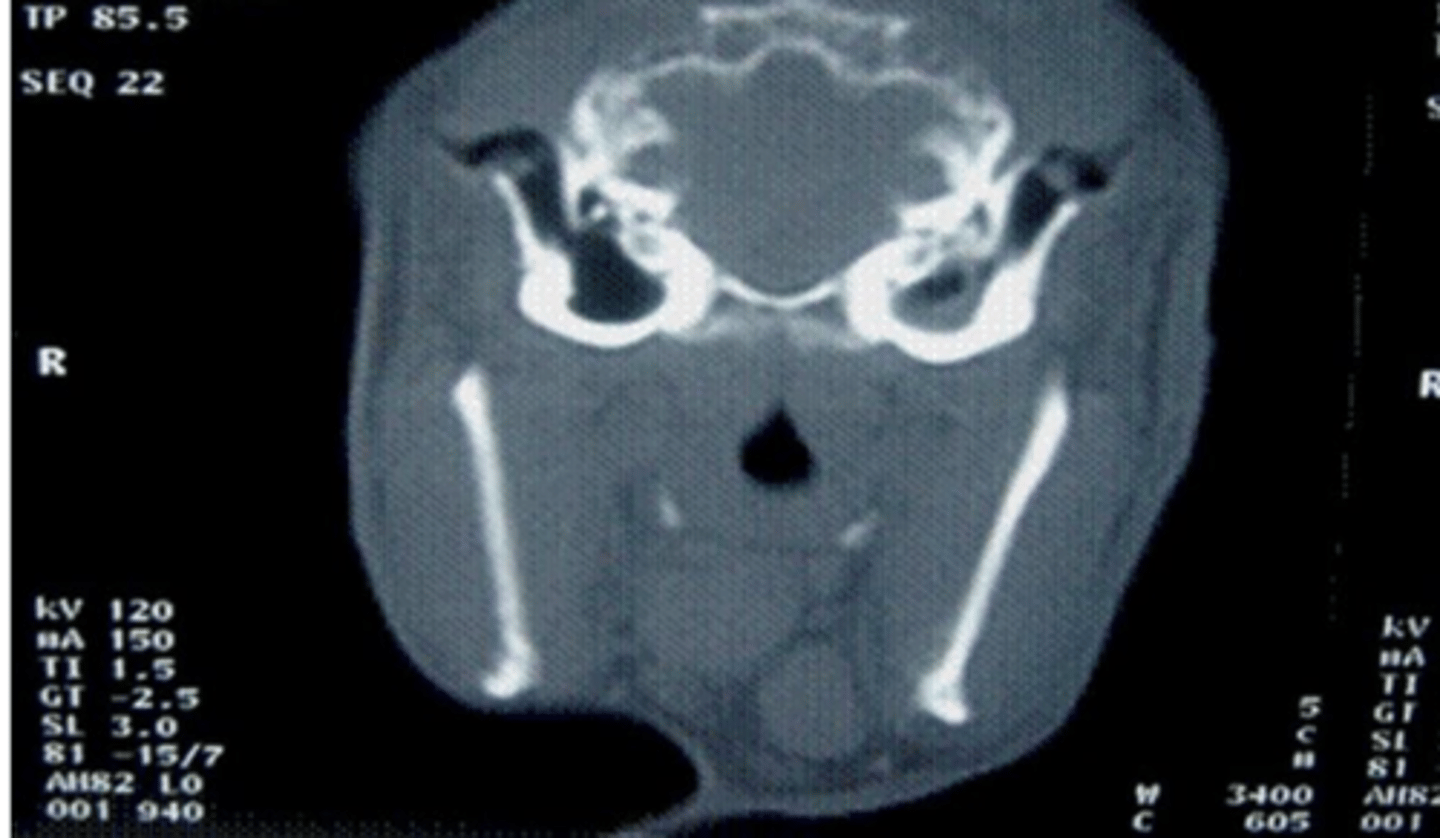

black, because they should be full of air

in a CT scan, how should the ear canals appear?

the right ear canal is filled with something (it should appear black)- could be fluid or tumor

what is wrong with this animal?